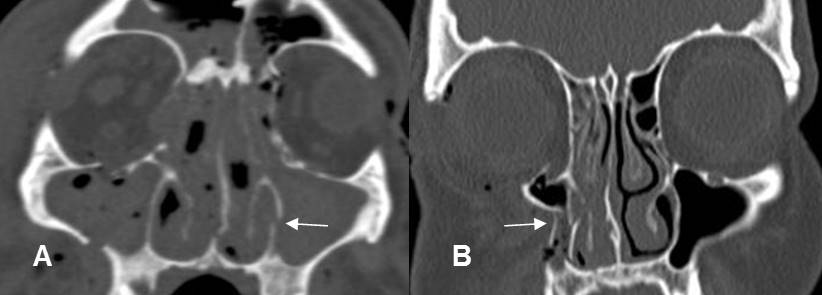

A: TAC coronal en ventana de tejido y B: TAC coronal en ventana de hueso.

Fractura deprimida en el piso de la órbita. Hay herniación de la grasa, pero el recto inferior mantiene su posición. (Flecha gruesa).